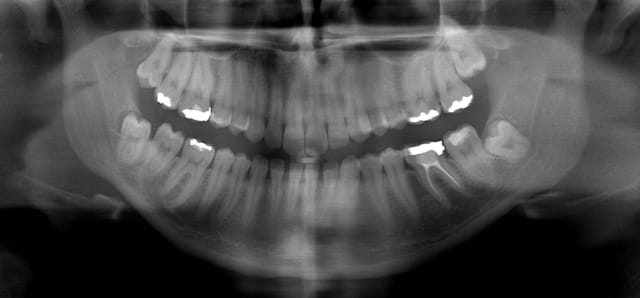

30/04/2010 à 00h49

Bon finalement j'ai fait mon choix, cone beam installé hier !

Vatech Ewoo.

Pour moi les plus :

- taille de champ variable: 5*5 8*5 8*8 12.5*8

- vraie combo pano/cone beam

- interface sympa

- artefact métallique limité

- Logiciel d'imagerie et planification implantaire très bien

quelques clichés d'essais